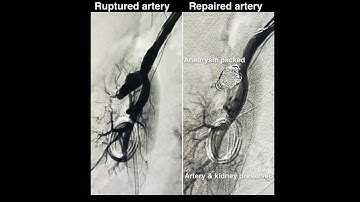

Renal Pseudo-aneurysm Embolization